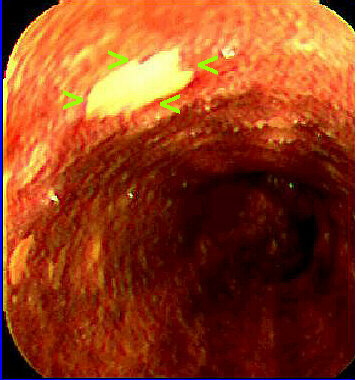

Ballon cytology: many "low grade" dysplastic squamous cells were seen. Increased N/C ratio, some binucleated cells, moderate nuclear hyperchromasia in other cells. At endoscopy, confirmation of the diagnosis, and identification of the dysplastic areas by negative lugol staining ( See article by Freitag et al. Dis Esophagus 1999;12:191-195.). Biopsy showed low grade intraepithelial squamous lesion. In Taquara, RS, Brazil, there is a high incidence of squamous cell carcinoma of the esophagus, and we are conducting a population surveillance with a special ballon for cell collection. This is one of the patients with dysplasia that were detected and treated (mucosectomy).